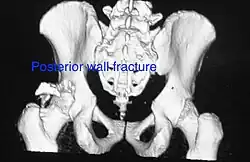

Posterior wall fracture as seen on 3-D CT scan -

| Posterior wall | This is the most common variety of acetabular fracture. It typically occurs due to dashboard injury; when a person travelling in a vehicle involved in a head-on collision, the force applied over the flexed knee travels along the femur bone to the head of the femur, breaking the posterior wall of the acetabulum. The head of the femur is dislocated outside the joint. | T shape | When a transverse fracture also had a vertical fracture line, it is called a T shape fracture. Here the innominate bone is broken in such a way that all three parts of it, the ilium, the ischium and the pubis are separated from one another. This is a three part fracture. Though both columns are broken, the weight bearing dome is still attached to the main part of the ilium and hence it is not a true fracture of both columns.